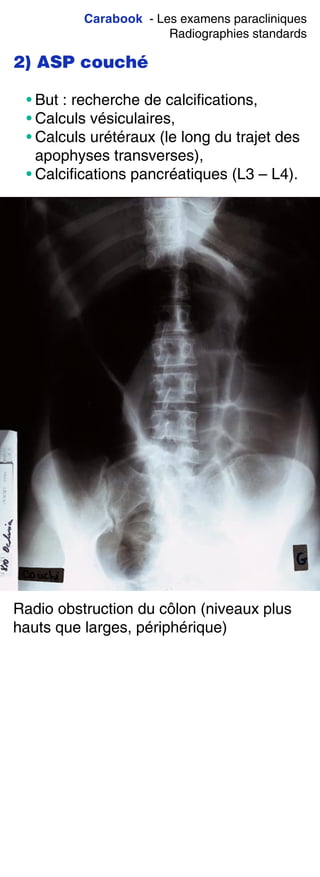

Mode d’emploi,